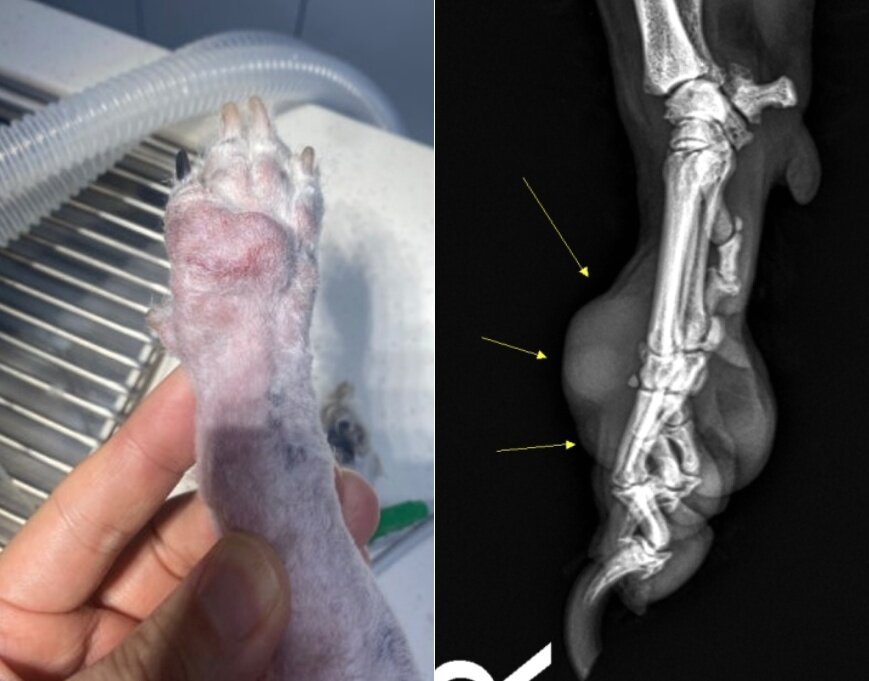

본문 이미지 - 13살 비숑프리제 소미의 오른쪽 앞발 발등에 생긴 악성 종양의 방사선 사진 (병원 제공) ⓒ 뉴스1

13살 비숑프리제 소미의 오른쪽 앞발 발등에 생긴 악성 종양의 방사선 사진 (병원 제공) ⓒ 뉴스1